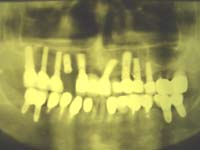

例1:40歳代女性、治療後17年経過(平成19年3月現在)

<主訴>

入れ歯を使用。咬み合わせが悪く、片頭痛・肩こり・顎関節症の症状有り。

<治療結果>

当院のインプラント治療(4本)により、主訴は消滅。現在もメンテナンスを行って頂き、問題なし。

治療前 治療後